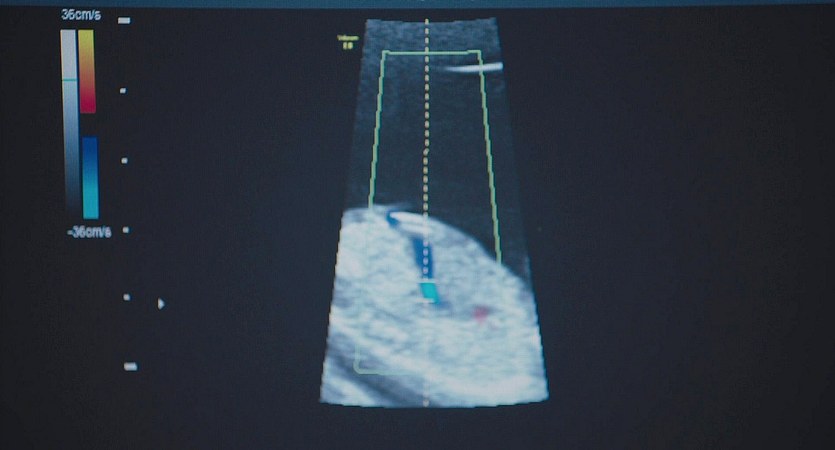

圖片名稱:Equity.2016_06436

圖源尺寸:Blu-ray 1080p